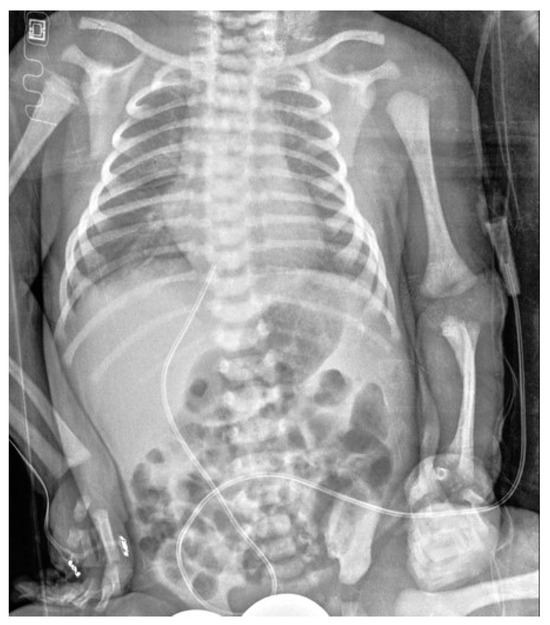

Conventional Radiology Evaluation of Neonatal Intravascular Devices (NIVDs): A Case Series

3. Results